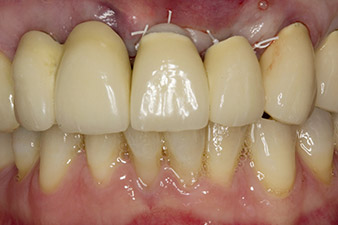

Después de la cicatrización primaria, los tejidos blandos se modelaron con ayuda del puente con base reconstruida. Dos meses después, se procedió a la exposición del área con una incisión de la cresta maxilar en sentido ligeramente palatino (figura 2).

orificio piloto utilizando el nuevo Implantmed y el contra-ángulo WS-56 L

Imagen 2: Dos meses después, se practicó un orificio piloto utilizando el nuevo Implantmed y el contra-ángulo WS-56 L (programa P1, transmisión 1:1). La refrigeración se realizó a través del tubo de spray colocado a la izquierda (para diestros).